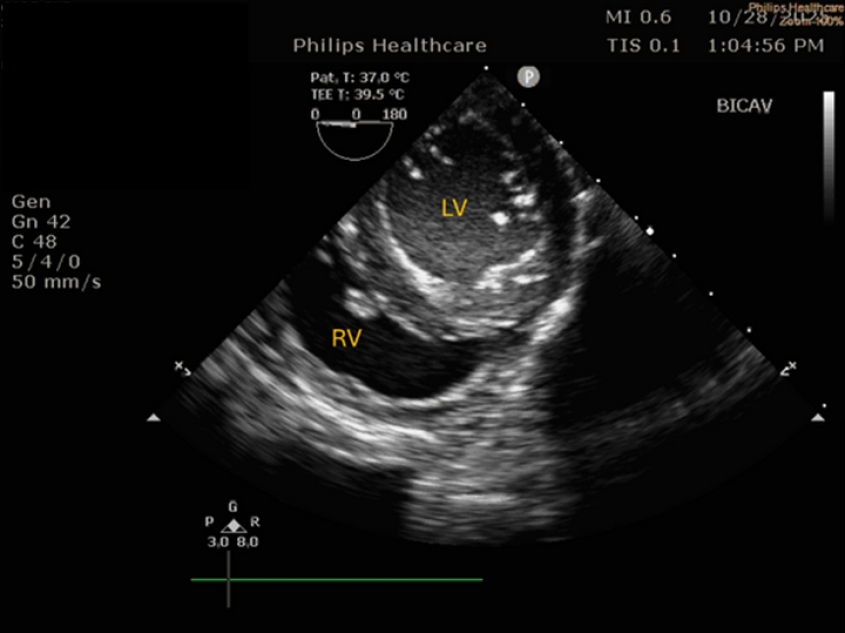

Caudal-esophageal short axis (CE SX)

The short-axis view of the left ventricle – which resembles a mushroom, is typically obtained in people through a deep transgastric location of the probe. This technique is challenging in dogs. An alternative is to obtain this view from a caudal esophageal location, although in our experience, this is not possible in large dogs. Complete, or near complete retroflection of the probe is necessary. The CE SAX view allows to observe all left ventricular walls contract simultaneously, which is useful in humans that may suffer from regional wall motion abnormalities. This problem, however, is much less common in dogs. The view is also useful for volume assessment, and to subjectively judge fractional shortening.